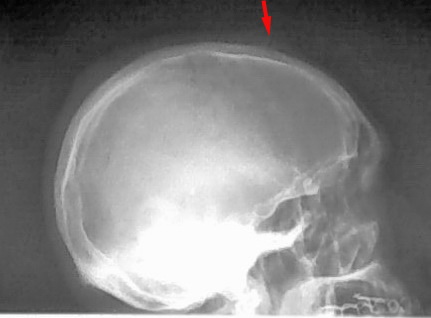

额顶部外伤3小时,请问箭头所指正常吗

未见明显凹陷骨折征象,要是锐器伤倒是支持支持,可结合患者外伤部位观察;另外头颅外伤即使没有骨折也并不代表没有问题,还是结合ct或mri检查好一些。

不象是骨折,现在很少人头颅外伤照平片,建议ct。

工作中查体非常重要,如果患者受伤的部位正好在箭头所指位置,那么就要高度疑似。